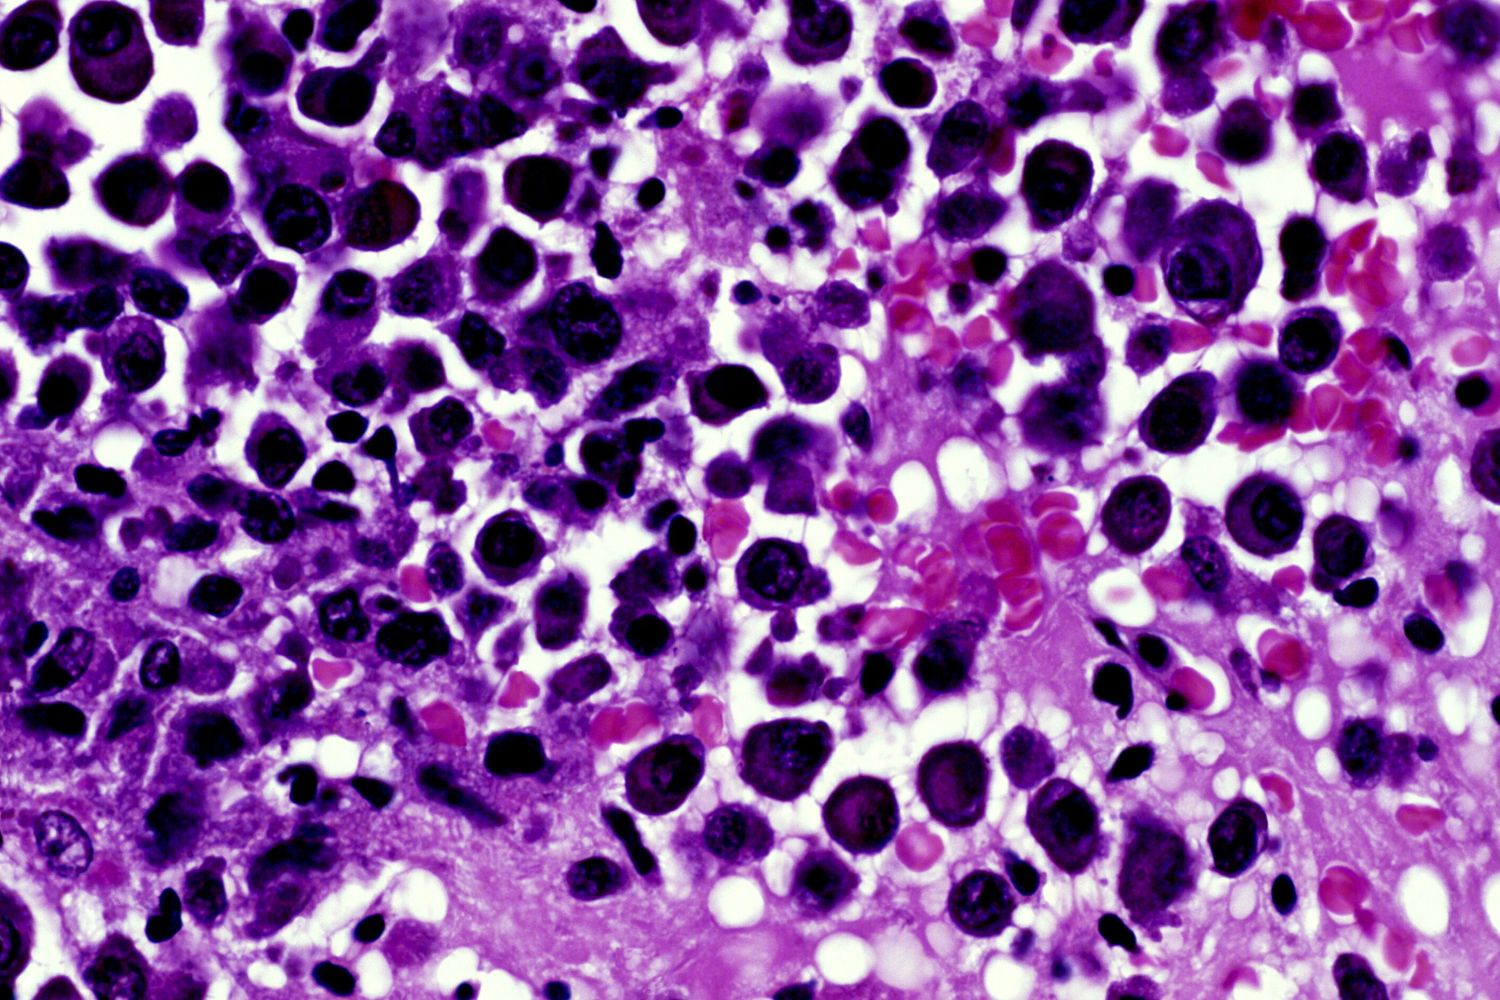

Lo studio, che ha coinvolto 494 pazienti, segna una svolta per chi è affetto da mieloma multiplo, il secondo tumore del sangue per incidenza, con 6.590 nuove diagnosi ogni anno in Italia. Risultati rilevanti anche per lo studio DREAMM-8. Entrambi hanno visto la combinazione di tre farmaci, in due diverse opzioni terapeutiche.